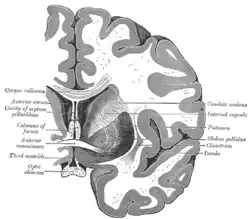

![]() Coronal section of brain through intermediate mass of third ventricle. (Putamen labeled at top.) | |

The putamen is a structure in the forebrain. Along with the caudate nucleus it forms the dorsal striatum. The caudate and putamen contain the same types of neurons and circuits – many neuroanatomists consider the dorsal striatum to be a single structure, divided into two parts by a large fiber tract, the internal capsule, passing through the middle. The putamen, together with the globus pallidus, makes up the lentiform nucleus. The putamen is the outermost portion of the basal ganglia. These are a group of nuclei in the brain that are interconnected with the cerebral cortex, thalamus, and brainstem. Basal ganglia include the dorsal striatum, substantia nigra, nucleus accumbens, and the subthalamic nucleus.

The caudate works with the putamen to receive the input from cerebral cortex. Collectively, they can be considered the "entrance" to the basal ganglia. Projections from the putamen reach the caudate directly via the caudolenticular grey bridges. The putamen and caudate are jointly connected with the substantia nigra, however the caudate outputs more densely to the substantia nigra pars reticulata while the putamen sends more afferents to the internal globus pallidus.